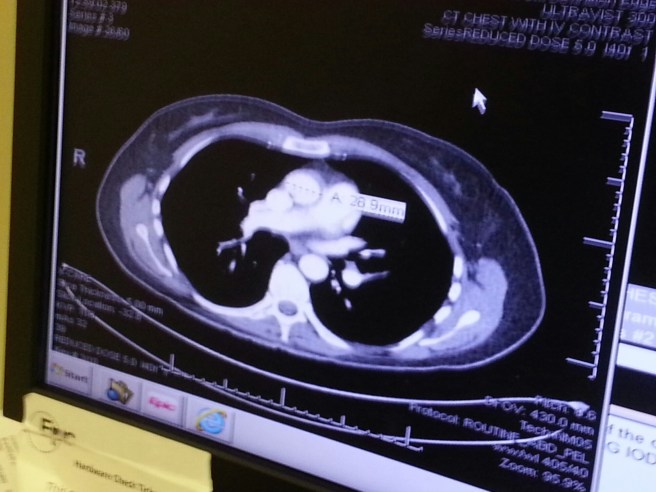

I had to wait an excruciating hour or so to get the results. Once I did, I asked to see my scans.

image

Yeah, it’s hard to understand and the tumors aren’t where you’d think they are on the image, but the point is: THEY SHRANK. Just like they were supposed to. The largest ones measured over a centimeter before and they are now measured in millimeters, very few millimeters. My immune system is kicking their little tumor asses. I hope your immune system is never tested in this way, but if it is, I hope yours is as ninja-like and unsparing as mine.

I said “tumor” in an Arnold Schwarzenegger accent, and Nurse Practitioner K (who was so happy to give me good news today since she’d been the one to break the bad news in September) laughed. Dr P came in and suddenly I found myself with the nickname “The Tumornator.” I’ll be back… (in twelve weeks, for a new scan.)